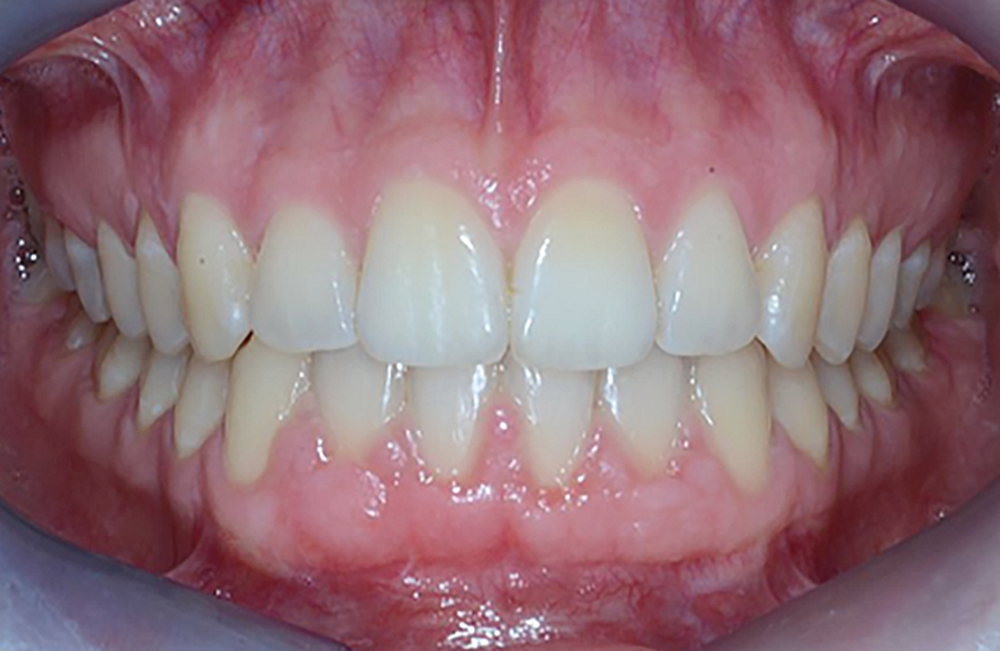

Le Pr Olivier Sorel insistera sur l’importance du respect des formes et des proportions anatomiques, pour éviter de voir apparaître, notamment chez les adultes, de très inesthétiques triangles noirs lors de la phase d’alignement (fig. 6a-b). Il présentera sa démarche diagnostique (évaluation de la forme des dents et de la dysharmonie dento-dentaire, fig. 7a-c) et l’intégration de la réduction amélaire proximale au plan de traitement, afin de s’assurer, en fin de traitement, la présence de papilles gingivales et donc d’un sourire harmonieux (fig. 8a-d).